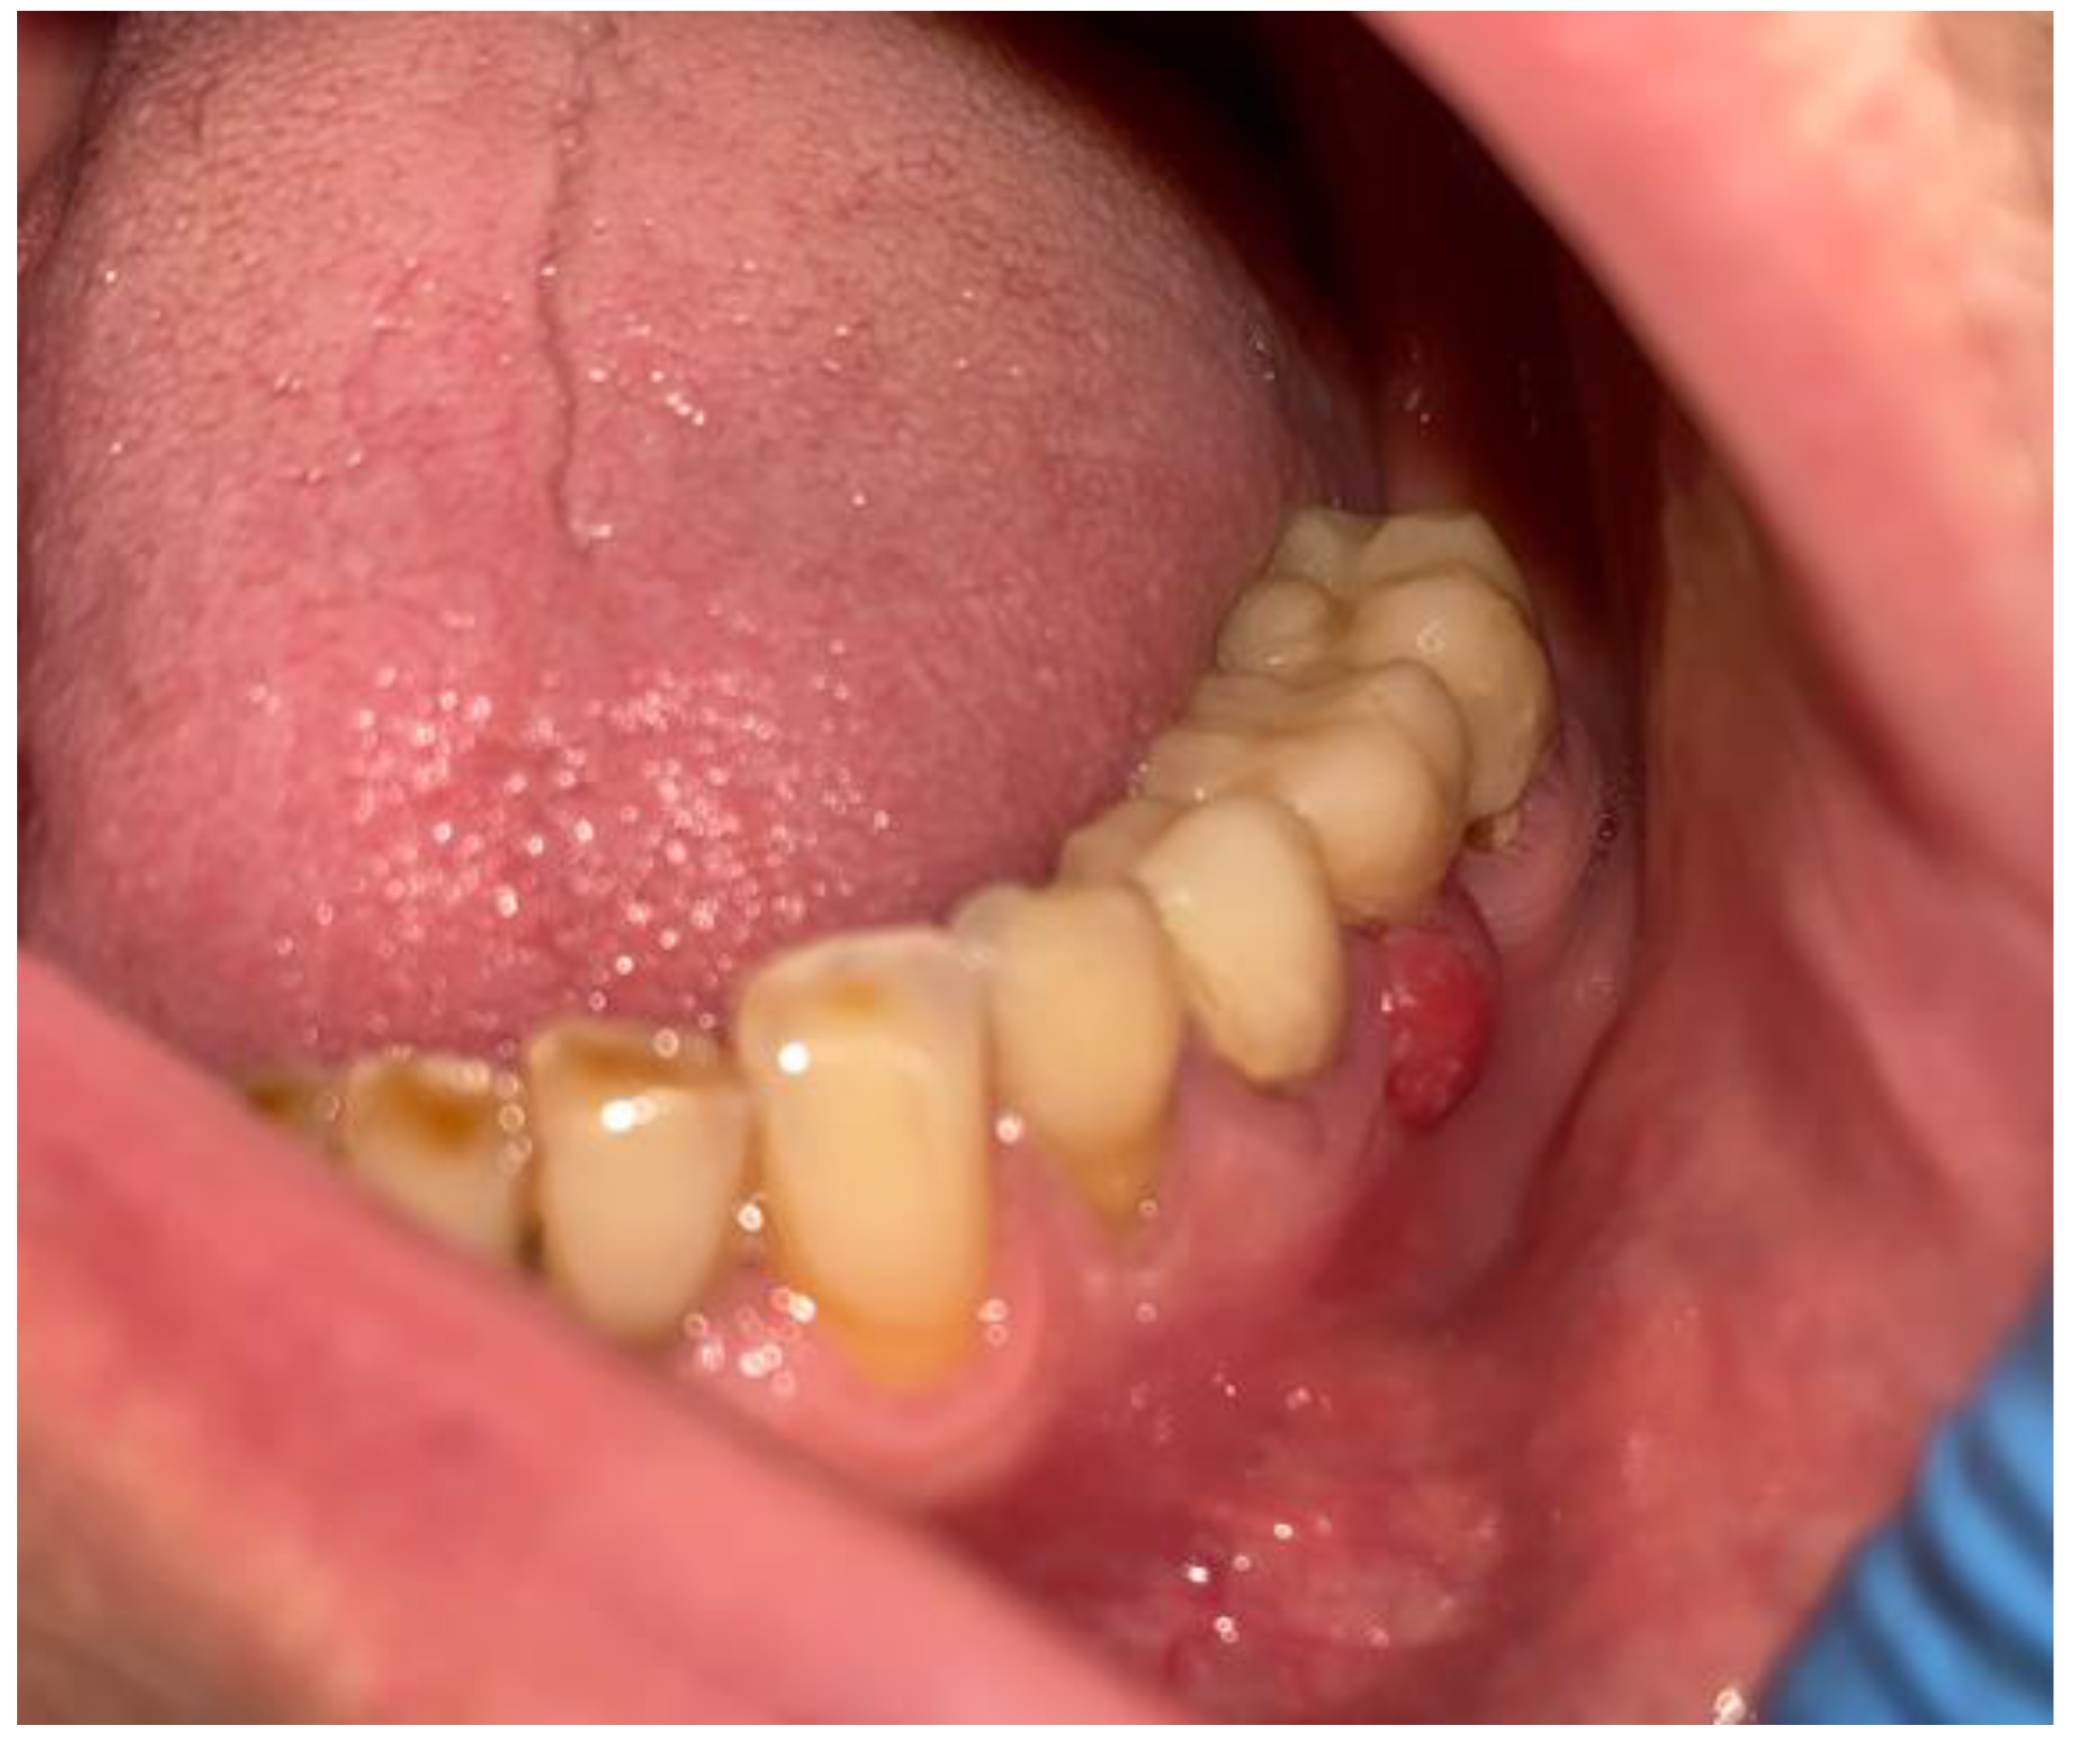

2. Case Description

- Elimination of all possible inflammation sources in the oral cavity and pre-surgical hygienization;